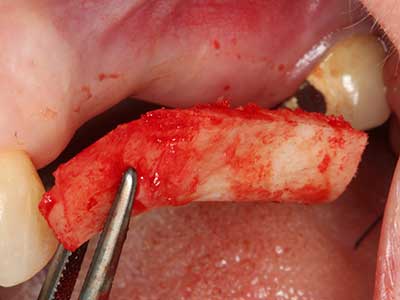

En la extracción de bloques óseos la piezocirugía también presenta ventajas adicionales: Además de la alta precisión en la osteotomía que ya se ha descrito antes, se ha comprobado que el uso de los delgados insertos de sierra resulta especialmente cuidadosas con el hueso. Frente a esto, sobre todo cuando se usan las fresas de Lindemann, cabe esperar pérdidas en la extracción significativamente más altas debido al mayor grosor de la parte frontal del cabezal (Lakshmiganthan, Gokulanathan et al. 2012). La separación basal que se necesita en particular en los injertos de bloque extraídos de forma retromolar se ve facilitada mediante sierras perpendiculares especialmente previstas a tal fin, lo que permite considerar que la cirugía piezoeléctrica es un procedimiento preciso y seguro para la obtención de bloques de hueso en el área retromolar (Happe 2007) (fig. 1-12).

Aplicación: Partición ósea / Cortical Split